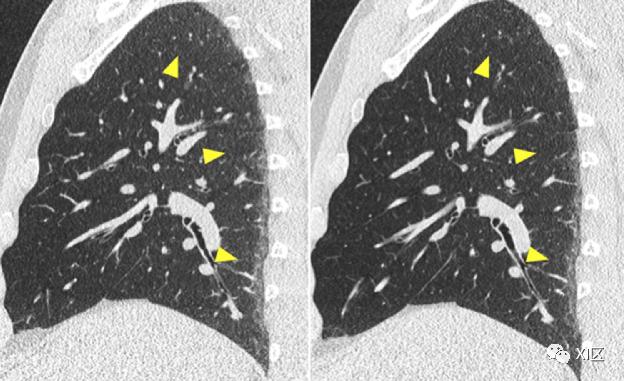

在低辐射剂量的各种临床应用中,评估消除电子噪声对图像质量的影响。与闪烁体探测器相比,临床前混合双源CT的光子计数探测器获取的肩部图像中的条纹伪影更少。Symons等人发现肺部、毛玻璃和肺气肿等模体等效海绵橡胶的HU单位稳定性更好,测量结果的再现性更好。这是进一步降低肺部成像中辐射剂量的一个重要先决条件,例如在肺癌筛查的背景下。在一项对30名接受低剂量胸部CT成像的受试者的研究中,光子计数CT显示了更高的诊断质量,肺、软组织和骨骼的图像质量分数显著提高,线束硬化伪影更少,图像噪声更低,肺结节检测的CNR更高,见图11。

图11 用临床前混合双源CT原型获得的低剂量肺扫描的实例。A:能量积分探测器图像。B:光子计数探测器图像,由于没有电子噪声,在低辐射剂量下表现出较少的图像噪声(箭头)和改善的CNR。在一项联合体模、离体和体内研究中,低辐射剂量下冠状动脉钙化积分(CAC)质量得到改善。10名志愿者的标准剂量(平均CTDIvol=5.4mGy)和低剂量(平均CTDIvol=1.6mGy)的CAC评分,光子计数CT明显优于常规CT,这是由于缺少低能量X射线光子的向下加权,没有电子噪声,加上钙软组织对比度提高。作者认为光子计数CT技术可能在进一步降低CAC评分的辐射剂量方面发挥作用。